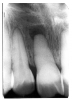

Figure 2 illustrates advanced enamel caries on the mesial surface of the premolar.

Figure 2 - Advanced Enamel Caries

Figure 2